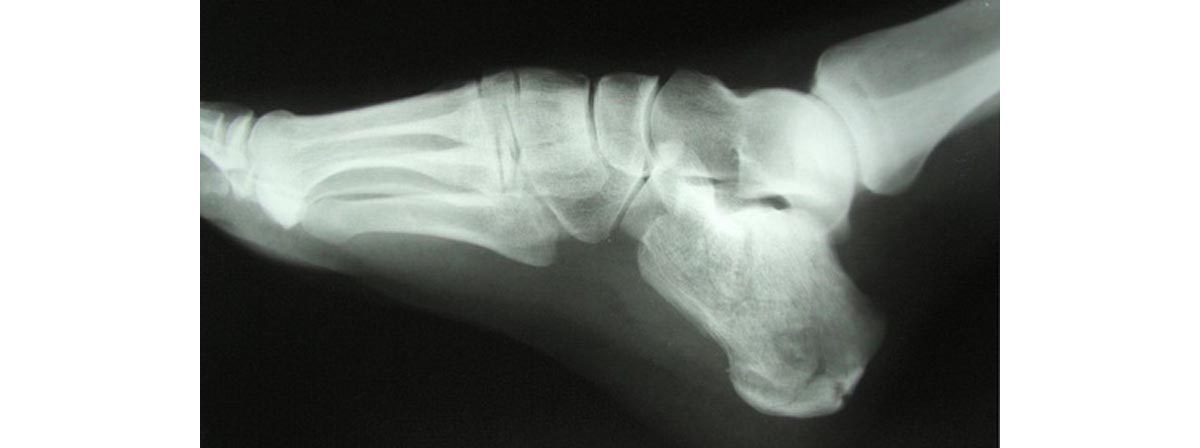

A Lisfranc fracture is an injury affecting the joints between bones in the middle of the foot. It is a painful injury that can sometimes be mistaken for a sprain. This is because fractures to the bones of the foot might not be as obvious as a broken arm or leg, as there are a lot of other supporting tissues and structures around bones in the foot.

Not all Lisfranc injuries result in bone fracture, as some instead involve the tearing of the ligaments and tendons in the area, and dislocation of the joints, while others will involve fracture(s) as well as soft tissue injury.

To diagnose a Lisfranc injury a doctor will inspect the foot and try moving the joints, as well as asking you to perform some movements. These would normally be painless, so pain may indicate the presence of an injury.

X-rays will also be taken to look for fractures. A CT scan and MRI scan can provide more detail but are not usually necessary for diagnosis. They may be needed if surgery is required, to determine the type and extent or repair needed.